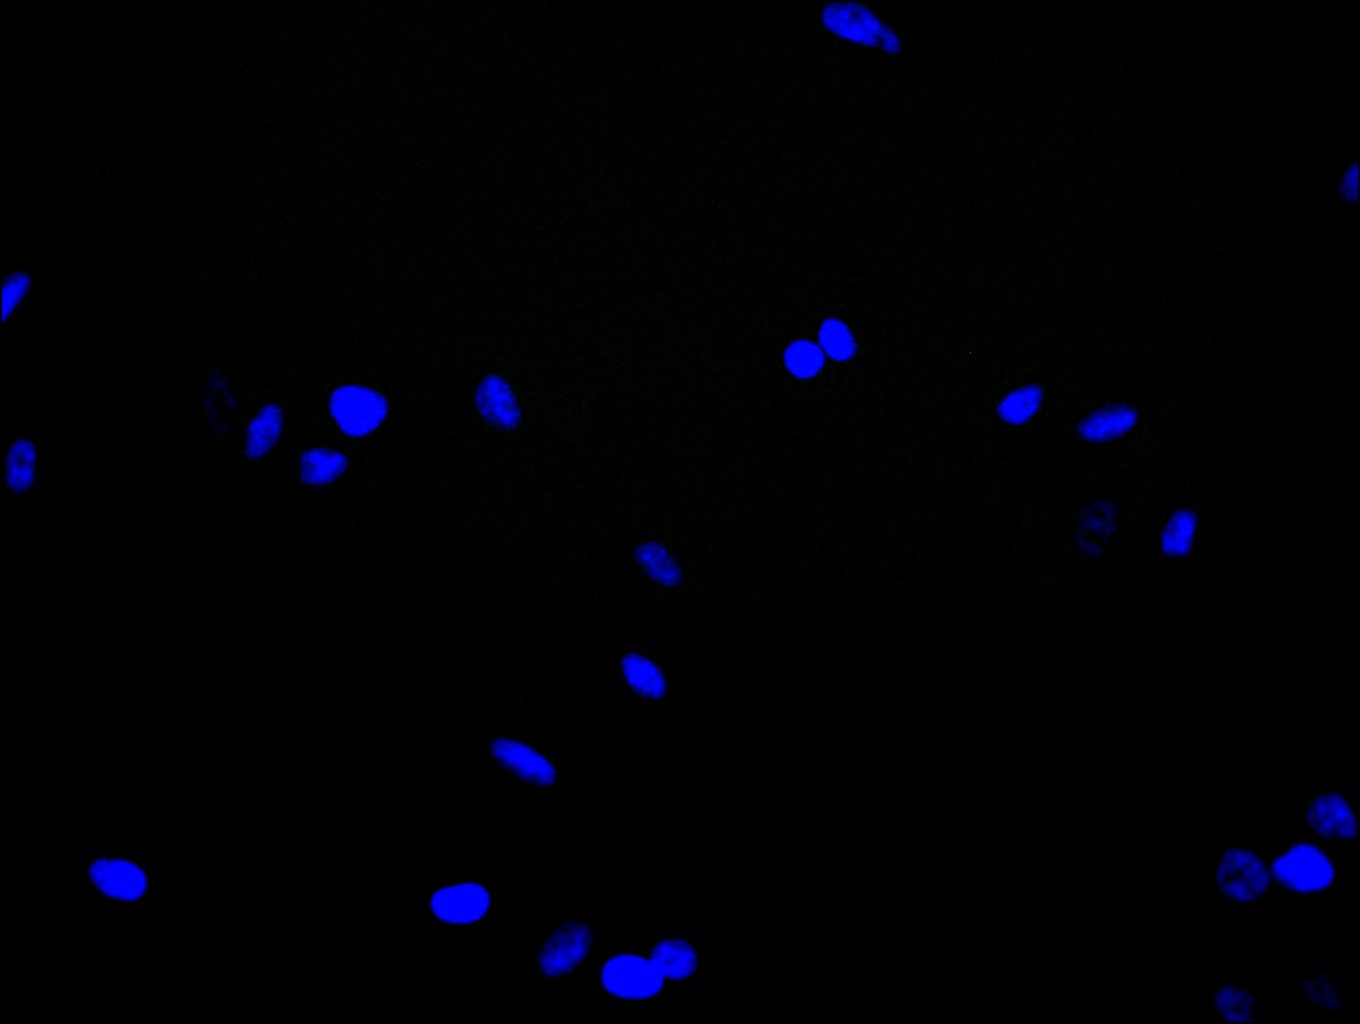

Immunofluorescence staining of Hela cell with 5% goat serum, counter-stained with DAPI. The cells were fixed in 4% formaldehyde and blocked in 10% normal Goat Serum. The cells were then incubated with the antibody overnight at 4C. The secondary antibody was Alexa Fluor 488-congugated AffiniPure Goat Anti-Rabbit IgG(H+L).

Immunofluorescence staining of A549 cell with 5% goat serum, counter-stained with DAPI. The cells were fixed in 4% formaldehyde and blocked in 10% normal Goat Serum. The cells were then incubated with the antibody overnight at 4C. The secondary antibody was Alexa Fluor 488-congugated AffiniPure Goat Anti-Rabbit IgG(H+L).